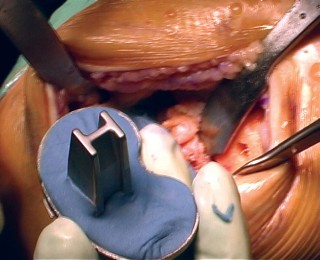

الخطوة 2: قطع عظم الفخذ (Femoral Cuts)

- الدليل داخل النخاع (Intramedullary Guide): يُستخدم دليل داخل النخاع لعظم الفخذ لضمان دقة القطع.

- ثقب كبير: يُحدث ثقب كبير في الجزء الأوسط من الشق بين اللقمتين.

- تحديد الزاوية: يُضبط الدليل داخل النخاع بزاوية 4 درجات ويُدخل في قناة الفخذ. يتم تركيب قالب القطع الفخذي البعيد (distal femoral cutting block) على الدليل.

- التثبيت والقطع: يُثبت القالب في مكانه ويُقطع الجزء البعيد من عظم الفخذ.

الخطوة 4: إكمال قطع عظم الفخذ وتحديد الحجم

- نظام التوجيه الخلفي: يُستخدم نظام توجيه خلفي لإكمال قطع عظم الفخذ.

- تحديد الدوران الخارجي: يُحدد المقدار الصحيح للدوران الخارجي لعظم الفخذ بناءً على المحور اللقمي الخلفي، والمحور فوق اللقمتين، وزاوية 90 درجة بالنسبة لمحور الساق (السطح المقطوع)، والمحور الأمامي الخلفي (خط وايتسايد).

- تحديد الحجم: يُوضع الدليل على الجزء البعيد من عظم الفخذ، ويُحدد حجم عظم الفخذ، ويُختار الحجم المطابق للمريض.